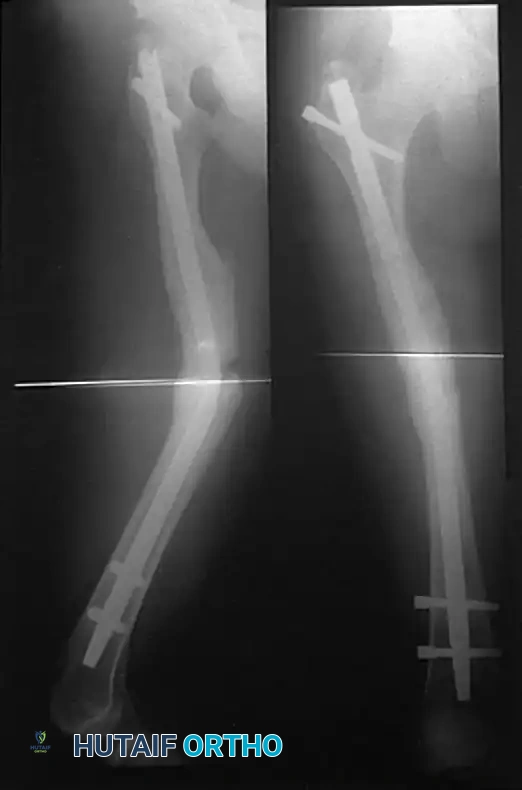

After reaming, recheck the position of the guidewire to confirm it remains at the level of the lesser trochanter. Apply axial traction to the leg to ensure proper length is restored.

Measure for the appropriate length of the nail using a radiopaque ruler placed over the guidewire. Ensure the ruler is countersunk to the exact depth you intend to seat the nail (typically 2-3 mm below the articular cartilage). This measurement is most accurately performed on the lateral fluoroscopic image.

Remove the entry portal tool and attach the selected retrograde nail to the targeting guide. Insert the nail over the guidewire. Advance the nail using gentle, controlled mallet strikes until it is seated at the level of the lesser trochanter proximally.

Maintain continuous traction on the leg during insertion to avoid acute shortening of the fracture. Check the lateral fluoroscopic image of the knee to ensure the distal end of the nail is properly countersunk beneath the articular cartilage to prevent patellofemoral impingement. Once the nail is at the proper level, the bead-tipped guidewire is removed.

Distal locking is performed first using the targeting guide attached to the nail insertion handle.

5. Insert the interlocking screws by hand until fully seated. Confirm length and position with AP and lateral fluoroscopy.

Proximal Interlocking (Perfect Circle Technique)

Before proximal locking, recheck the overall alignment and length of the femur. A Bovie cord can be stretched from the anterior superior iliac crest, over the middle of the patella, to the middle of the tibial plafond to confirm the mechanical axis.

Proximal locking is performed freehand using the "perfect circle" technique.